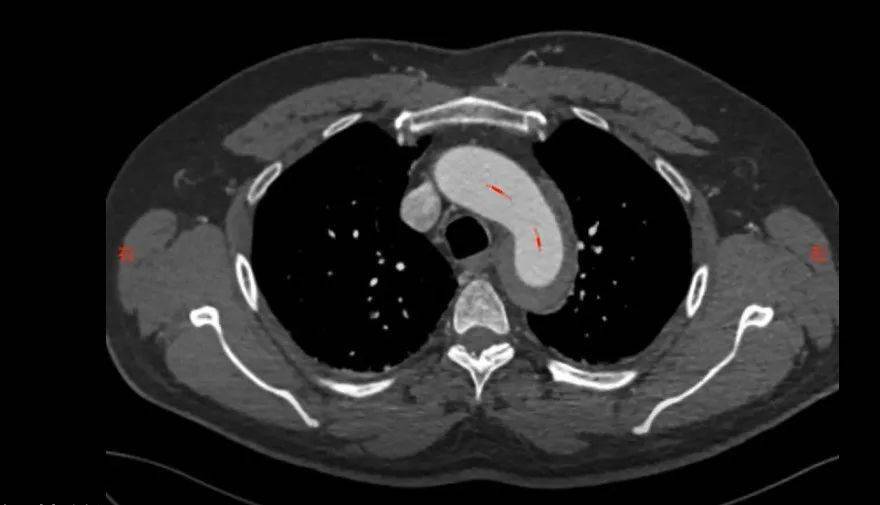

术前cta影像(箭头所指为升主动脉破口)

升主动脉内可见套筒样改变,非常典型的主动脉夹层.